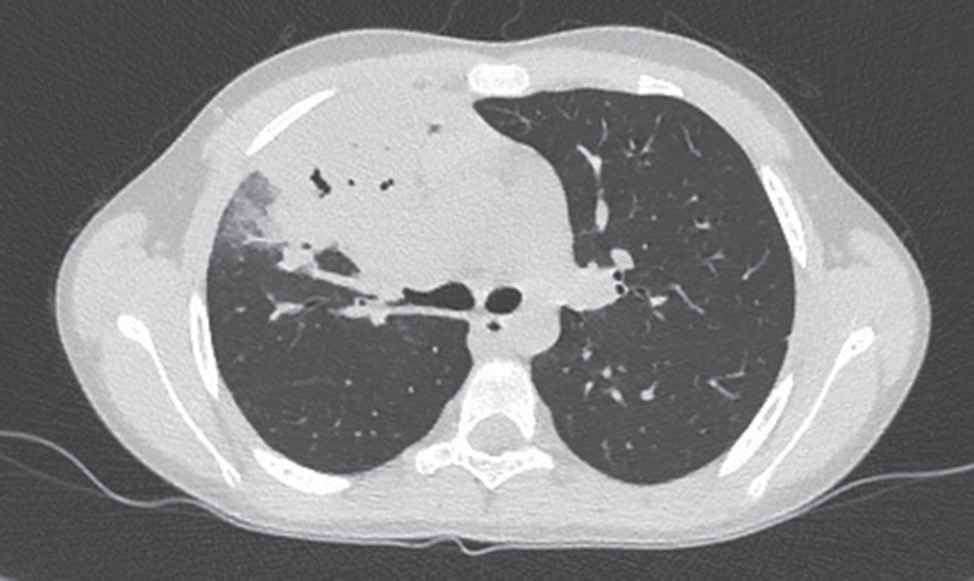

18.05. МСКТ-ангиография ОГК: определяются увеличенные бронхопульмональные лимфоузлы справа, умеренно сдавливающие бронх В3 и правый верхнедолевой бронх, оттесняя сосуды. Складывается впечатление о невыраженном краевом накоплении контрастного препарата капсулой лимфоузлов, а также о наличии зоны некроза (пониженной плотности, не накапливающей контрастный препарат) в центре. Выявленные изменения внутригрудных лимфоузлов могли бы свидетельствовать в пользу туберкулезного их поражения, однако изменения в легочной ткани этому не соответствуют. Ателектаз S3 вполне типичен для микоплазменной пневмонии, протекающей с реактивной гиперплазией лимфоузлов (рис. 3).

Рис. 3. КТ органов грудной клетки ребенка Н., 8 лет 7 мес., 21.05

Fig. 3. Chest CT of the child N., 8 years 7 months, 21.05